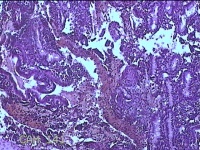

宫颈管组织

性别

女

年龄

33岁

临床诊断

异位妊娠

一般病史

停经52天,阴道流血12天。

标本名称

大体所见

灰白暗红色不规则碎组织4.3x3.3x1.2cm一堆。